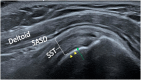

The rotator cuff is a group of four muscles and tendons surrounding the shoulder joint providing it strength and stability. The rotator cuff consists of the subscapularis, supraspinatus, infraspinatus and teres minor. Many shoulder complaints are caused by rotator cuff pathology such as impingement syndrome, tendon tears and other diseases e.g. calcific tendonitis. Diagnosis starts with clinical history and physical examination, after which imaging is often used to help confirm clinical findings depending on the differential diagnosis. The aim of the article is to review the frequently used imaging modalities to assess the rotator cuff and cuff-related disease, specifically focusing on radiography, ultrasonography and magnetic resonance imaging. This article will outline the advantages and disadvantages for each modality and illustrate typical radiological findings of common rotator cuff pathologies.